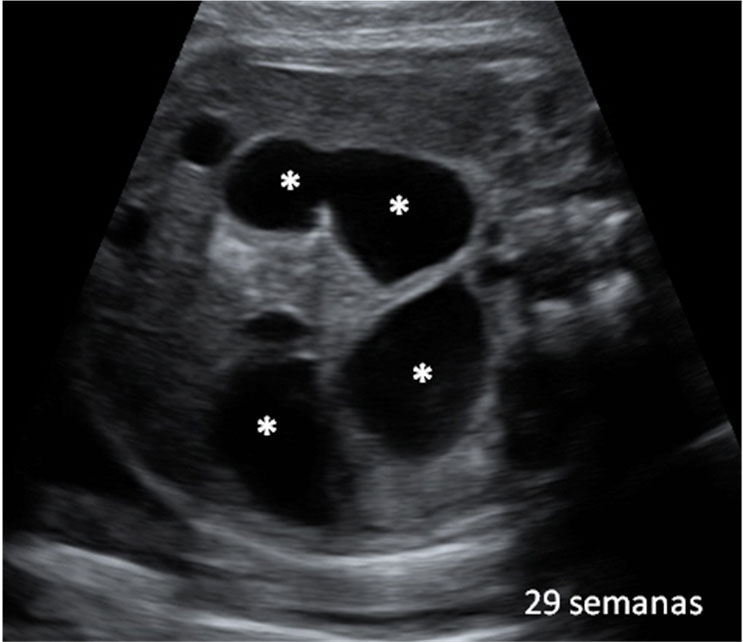

Imagen ecográfica de la dilatación de asas intestinales -marcadas con un asterisco (*)- por causa de una obstrucción en un feto de 29 semanas.

Dilatación de asas intestinales

Imagen ecográfica de la dilatación de asas intestinales -marcadas con un asterisco (*)- por causa de una obstrucción en un feto de 29 semanas. Está anomalía se diagnostica con frecuencia después de la semana 20. Ecografía Embarazo 2D y 3D - SEMANA 20 Ecografía Embarazo 4D - SEMANA 20